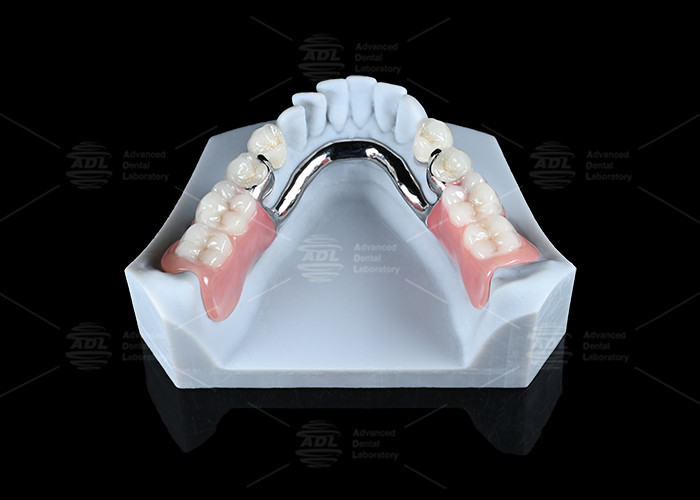

Stud Attachments Used in Tooth-Supported Overdenture

Stud Attachments Used in Tooth-Supported Overdenture

Stud Attachments Used in Tooth-Supported Overdenture。China Strong Locator Attachments Manufacturers, Suppliers。Digital Designed Milled Titanium Partial Metal Stud。

Nesbit | Partial Denture – Direct Dental Prosthetics

Bolt Attachment changes Partial Denture Prosthodontics - Suginaka “Riegel

BoltAttachmentchangesPartialDentureProsthodontics-Suginaka“Riegel

Koh-ichiSuginaka

Nesbit | Partial Denture – Direct Dental Prosthetics

Bolt Attachment changes Partial Denture Prosthodontics - Suginaka “Riegel

■商品名■

BoltAttachmentchangesPartialDentureProsthodontics-Suginaka“Riegel

■著者■

Koh-ichiSuginaka